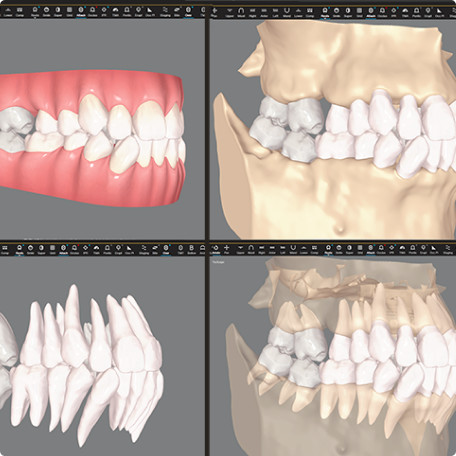

CBCT integration allows you to see more than ever for more informed treatment planning.

Auto-generates a 3D model with roots, crown, and bone for more-informed treatment planning.

Shows real root renderings and bone visualizations based on actual scan data.

Helps doctors leverage their expertise across a broad range of malocclusions to confidently expand care.